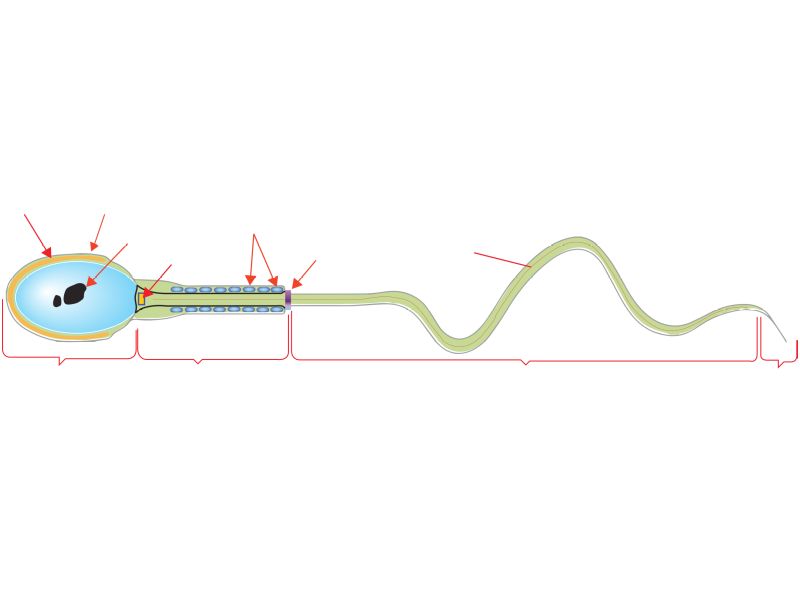

Spermatozoa

- Head

- Contains nucleus

- Dense chromatin

- Acrosomal cap anterior over nucleus

- Midpiece

- Mitochondrial sheath

- Small amount cytoplasm

- ATP for flagellar motility

- Tail

- Principle piece

- End piece

- Microtubuli for movement